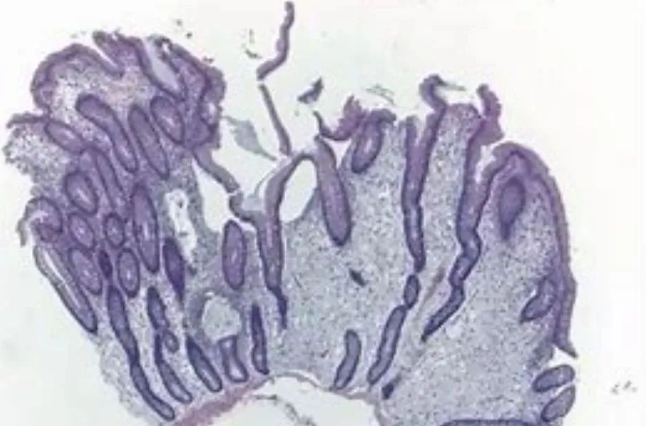

检查结果证实了大家的推测,患者胃镜提示:置底、体见弥漫性大小直径约0.5-2.0cm广基隆起,表面粗糙,边界清楚。胃窦见一大小约5x13cm隆起,呈分叶状.表面粘膜粗糙,边界尚清楚。肠镜见全结肠弥漫性大小约0.5-1.0cm 广基隆起。胃窦较大病变予取材送检,病检回报示:错构瘤性息肉。患者胃窦巨大病变,若不及时切除癌变风险极大,但患者年纪较轻,如果进行传统外科胃大部分切除术对患者后续生活质量影响较大。经讨论后,为患者进行胃镜下胃窦病变粘膜下剥离术为最佳手术方式,但是因患者病变巨大,手术难度大,剥离过程中出血及穿孔风险极大,这也为手术增加了不少难度。与此同时患者强烈要求就在本院进行手术治疗。

本着信任和解决难题的初衷,经过全科病历讨论后为患者制定了详细的手术方案及术前准备,历时六个小时,终于成功为患者完成了内镜下胃窦巨大肿物ESD 术,瘤体完整剥离,创面无残留,术中出血約50m1,离体标本大小5. 0X13CM。内镜诊断。术后病检符合P-J息肉诊断。

黑斑-息肉综合症 (Peutz-Jeghers syndrome, PJS) 是一种以胃肠道多发性息肉、皮肤黏膜色素沉着、患癌倾向为特征的常染色体显性遗传病。PJ 型错构瘤性息肉可出现在全消化道,其中以小肠最常见。胃肠道息肉可以导致慢性出血和贫血,还可以引起反复发作的肠梗阻和肠套叠,甚至癌变,患者需要多次外科手术治疗。黑斑-息肉综合征中的“黑斑”主要因为皮肤黏膜色素沉着,主要表现为自儿童期出现嘴、眼、鼻孔、肛周以及颊粘膜深蓝色至深褐色斑,手指色素沉着斑常见。大多黑斑在青春期和成年期可消退或变淡,但黏膜处比如嘴唇黑斑却很难消退。所以也有专家称其为“一眼望出来的病”。

黑斑息肉综合症患者发生多种恶性上皮肿瘤(结肠、 胃、胰腺、乳腺以及卵巢癌)的风险增加。黑斑-息肉(P-J)综合症中发挥什么样的作用?患者在因P-J综合症导致的长期腹泻、便血或贫血来做消化内镜检查时,可以帮助发现消化道多发的息肉,这些息肉多大小不定,小者仅为针头般大小的隆起,大者直径可达10cm,多为0.2~0.5cm,表面光滑,蒂的长短、粗细不—,也可无蒂,较大息肉可呈结节菜花样。内镜下活检送病理可以确定息肉性质,结合患者临床表现可以帮助确诊该疾病。